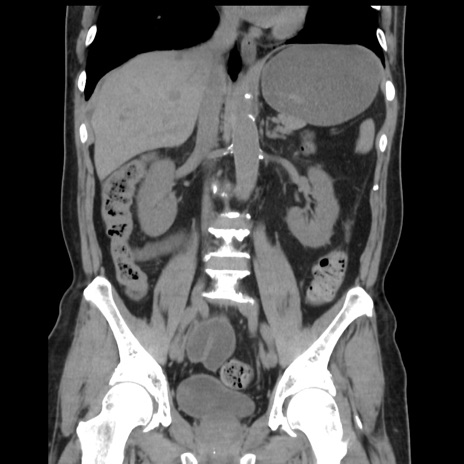

症例16(冠状断像)

【症例】 70歳代男性

【主訴】 腹痛、嘔吐

【現病歴】 約1ヶ月前より間欠的に腹痛と嘔吐あり、当院消化器内科を受診したところCTで多発する肝臓のLDAを指摘され、精査中であった。以降は消化器症状は安定していたが、2日前より嘔気と腹痛があり、同日より排便・排ガスが消失した。改善認めず、 本日、救急外来を受診した。

【既往歴】 大腸ポリープ切除後。

【身体所見】意識清明・会話良好、BT 36.3℃、BP 127/80mmHg、 P 80bpm、腹部:膨満あり、平坦・軟、上腹部正中および下腹部正中に圧痛あり、反跳痛なし、筋性防御なし。

【データ】WBC 7200、CRP 0.77